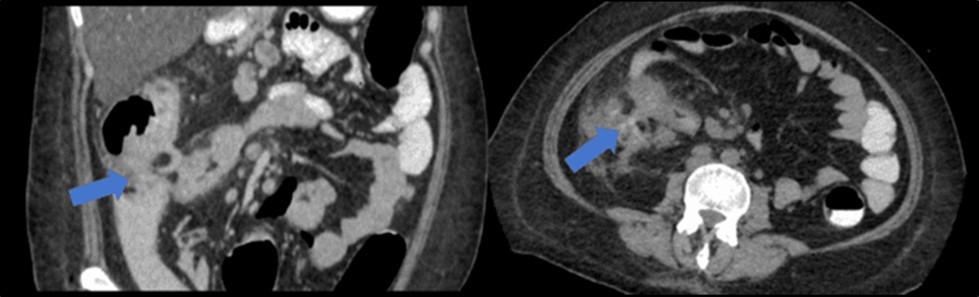

There was no evidence of malignancy or IBD seen during both endoscopic procedures. Computed tomography (CT) scan of the whole abdomen was done which showed inflammatory changes involving the cecum and adjacent duodenum and ileum with coloenteric fistulae. There was noted progression of abdominal lymphadenopathies as well as ascites. Main consideration was an infectious disease process (i.e. TB) (Figure 2, Figure 3, Figure 4 to Figure 5).

Figure 4.Coronal and axial view of the abdomen, the blue arrows pointing towards the suggestive communication to the duodenum

Coronal and axial view of the abdomen, the blue arrows pointing towards the suggestive             communication to the duodenum